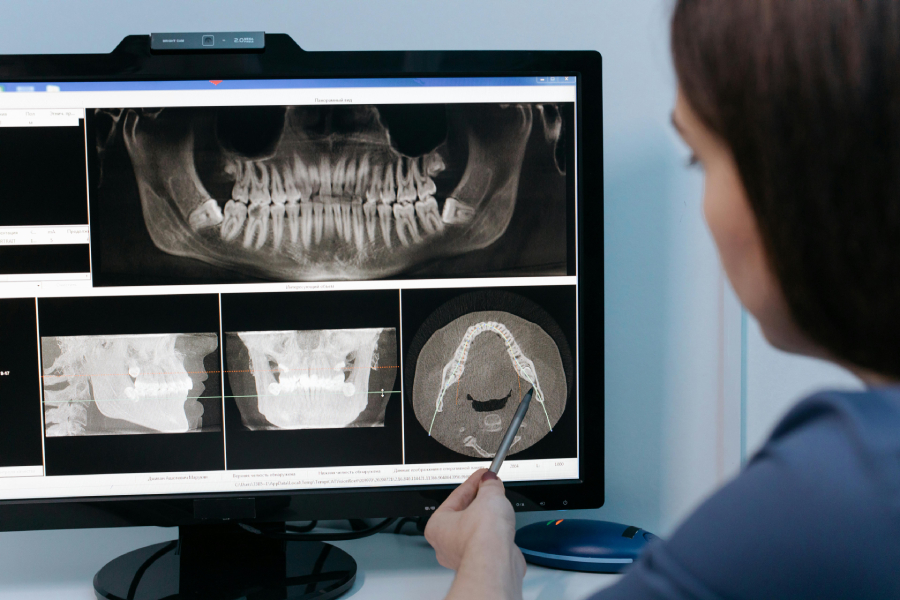

Κατά τη διάρκεια της ορθοπαντομογραφίας, ο ασθενής τοποθετείται κάτω από το μηχάνημα και το ακτινολογικό μηχάνημα κινείται γύρω από το κεφάλι, λαμβάνοντας την εικόνα από διάφορες γωνίες. Ο οδοντίατρος ή ο ακτινολόγος θα σας ζητήσει να παραμείνετε ακίνητοι για λίγα δευτερόλεπτα, ενώ το μηχάνημα καταγράφει την εικόνα. Η διαδικασία είναι γρήγορη, διαρκεί μόλις μερικά λεπτά, και είναι ανώδυνη.